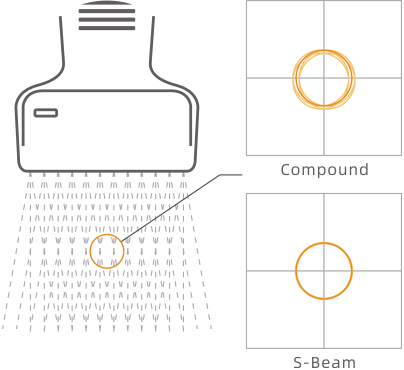

This technology traces and analyzes image information on multi-direction to suppress artifacts that come from tissue movement and rotation. The image quality and real-time capability are greatly boosted in special compound imaging.